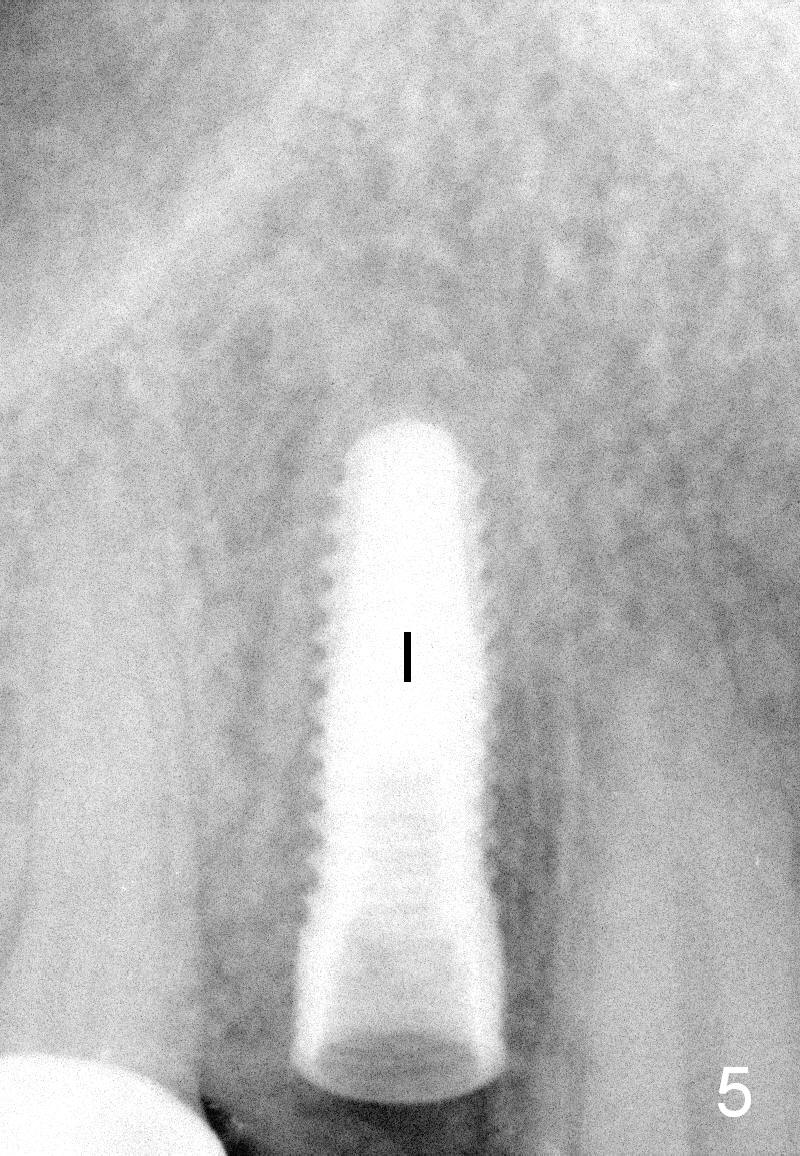

A 66-year-old man has lost several teeth (Fig.1,2). There is a particularly wide mesiodistal space for the site of #5 (Fig.1), probably due to distalization of the tooth #4 under heavy occlusion (Fig.2 arrow). A 4 mm tissue punch is used for access, followed by 1.6 mm pilot drill (Fig.3). After trajectory adjustment, a 2 mm parallel pin is inserted (Fig.4); later the osteotomy is moved distally (arrow). Finally a 4.5x14 mm implant is placed (Fig.5 I). Due to limited access, the implant is placed a little deeper than necessary; the gingival cuff of an abutment has to be longer (Fig.6 A: 5.8x4(3) mm). An immediate provisional is fabricated (Fig.7,8 P). The provisional looks wide (Fig.7). When the implant osteointegrates, limited orthodontic treatment will be done to idealize the space of #5 as follows.